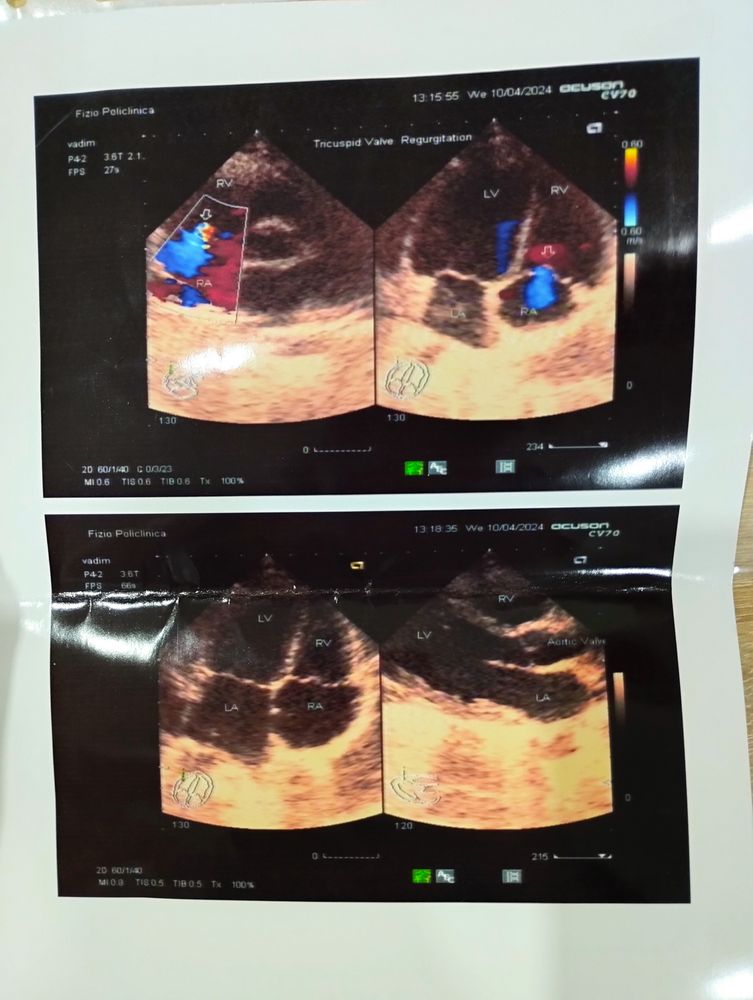

Недостаточность ТК клапана, насколько это опасно?(Фото)

Здравствуйте, вчера с ребенком были на УЗИ сердца, проходили для себя, врач попался не разговорчивый, напугал всякими медицинскими терминами, а потом вообще сказал, что восполнения сердца, у меня паника, Я записалась к кардиологу платно, но запись только через 2 недели. Этот диагноз опасен для здоровья? Нужно ли ограничивать физическую активность ребёнка?